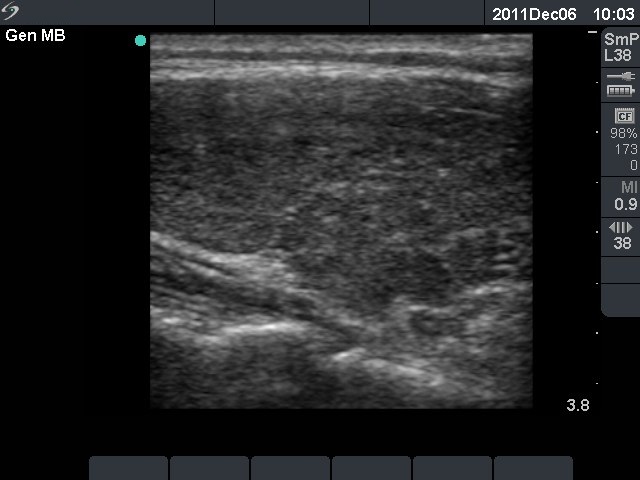

Second examination 3 months later (3rd row of images)

Clinical presentation: the complaints of the patient had decreased.

Palpation: no abnormality.

Functional state: euthyroidism with TSH-level 3.60 mIU/L, FT4 13.1 pM/L.

Ultrasonography: the degree of hypoechogenicity and the previously increased vascularization have decreased, as did the size of the thyroid.

We suggested follow-up examination with yearly TSH determination, in the case of pregnancy at once.